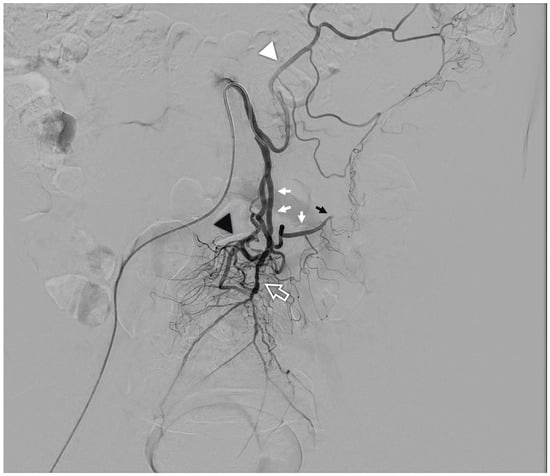

Vascular malformations involving the splanchnic circulation represent a heterogeneous and infrequent subgroup, in which detailed knowledge of the regional arterial and venous anatomy is essential. The IMA arises from the abdominal aorta and supplies blood to the left portion of the colon (from the point of Cannon–Bohm at the distal third of the transverse colon to the sigmoid colon) and the upper two-thirds of the rectum, while the IMV drains the corresponding venous territories into the portal circulation. Several clinically and surgically relevant anatomical variants of the IMA have been described, including differences in caliber and development (from hypoplasia to rare absence), variations in the level of origin relative to the typical L3 level, and exceptional origins from a common trunk with other visceral arteries [6] (Figure 1).

Figure 1. Arteriography of a normal inferior mesenteric artery: from the vessel arise the left colic artery (white arrowhead), the main sigmoid artery (white arrows) which continues into the marginal artery of Drummond (black arrow); the terminal branch is the superior rectal artery (white contour arrow) from which typically arise an accessory sigmoid branch (black arrowhead).